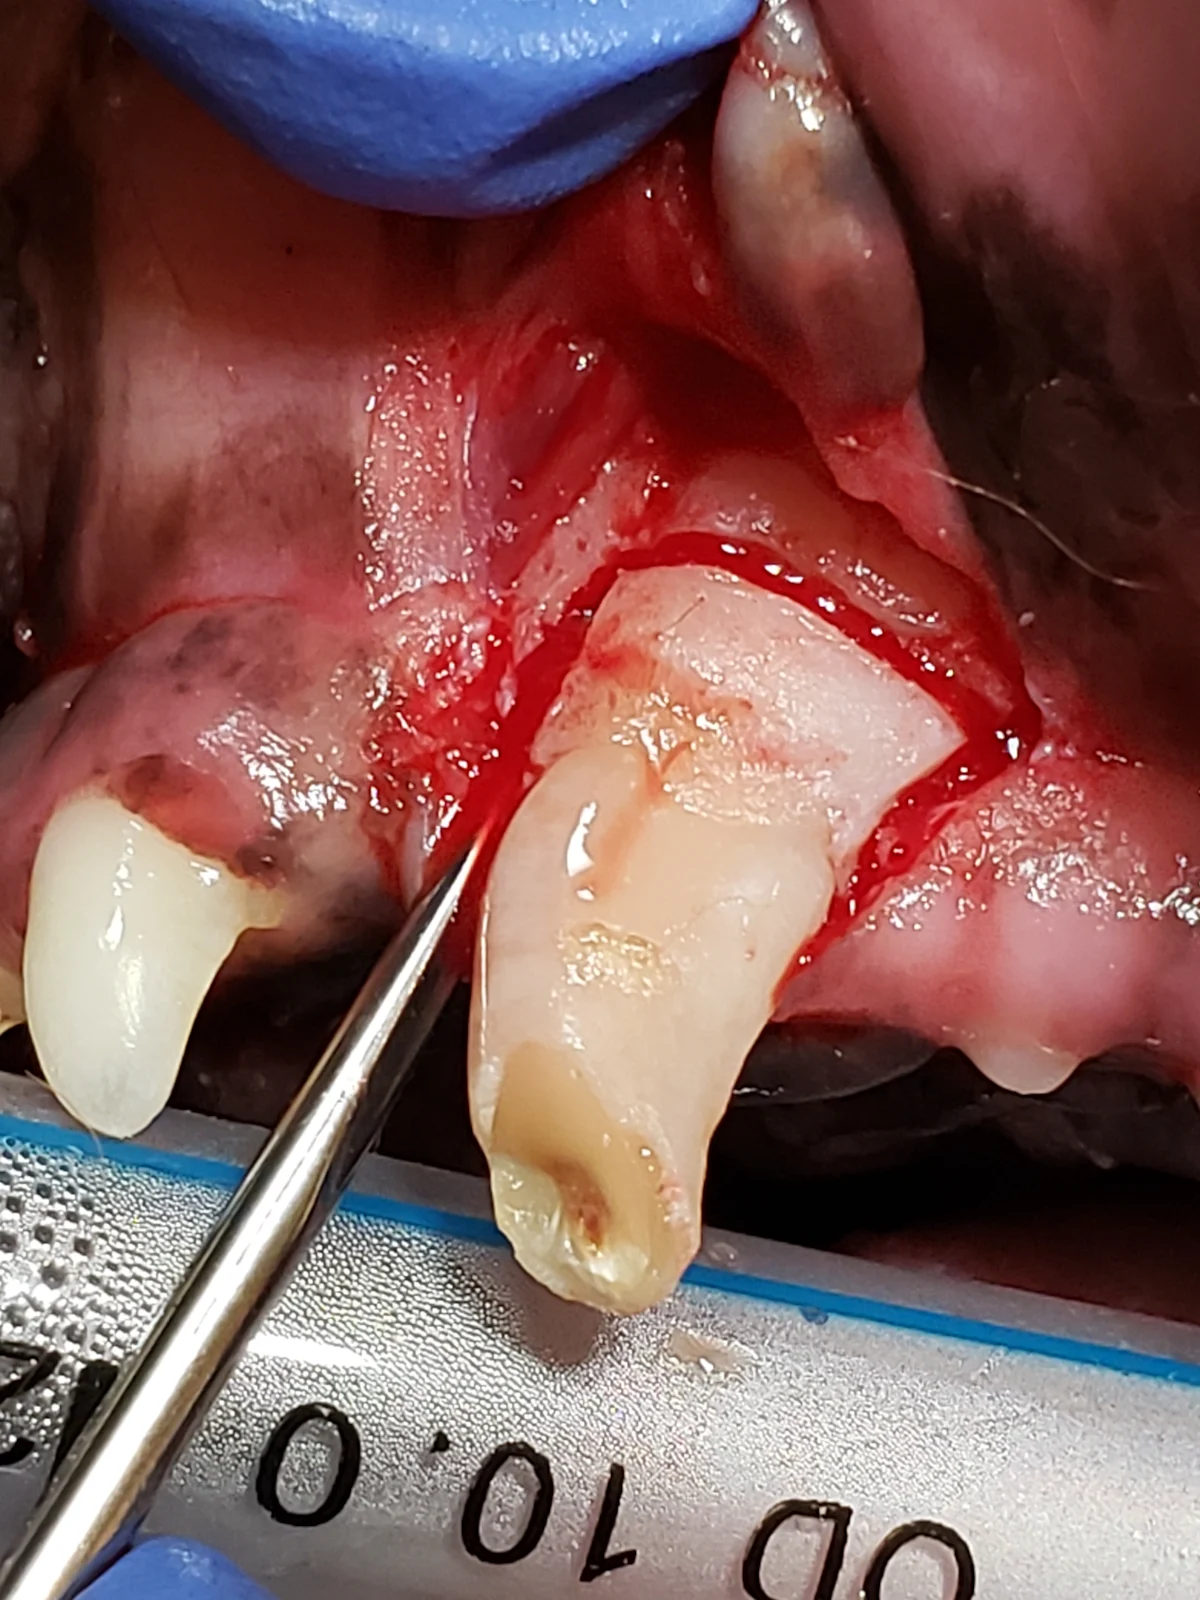

Step 2: Make Gingival Flap Releasing Incisions

Make releasing incisions for a full-thickness mucoperiosteal flap through the attached gingiva, past the mucogingival line, and at least a couple of millimeters into the alveolar mucosa to provide adequate exposure.

Rectangular Flap

A rectangular flap is created by making a mesial incision and a distal incision angled away from the tooth, following the distally curving position of the root. Releasing incisions should extend at least to the level of the widest part of the root and should be slightly divergent from each other, keeping the alveolar mucosa at the base of the flap wider than the coronal aspect with the attached gingiva, to provide enough tissue for closure. A flap wider at the gingival margin is important if an oronasal fistula is present. Making releasing incisions 1 to 2 mm from the outline of the tooth edge (dotted lines) places the incisions over bone, enhancing access to the periodontal ligament space and supporting the suture line following closure. In the author’s experience, this flap design provides optimal accessibility for tooth elevation and does not result in disruption of blood supply during healing.